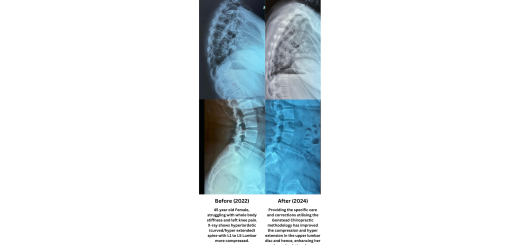

L5 Lumbar Disc Regeneration

by ACCSing · 21 June, 2024